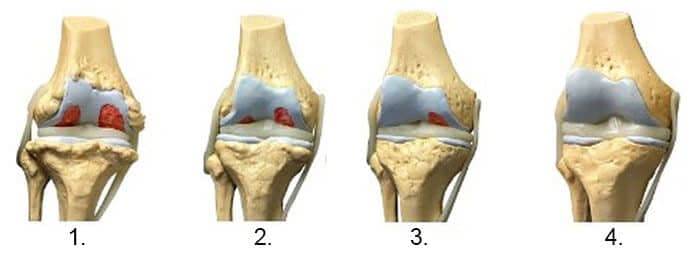

1. Nedostatak zajedničke prehrane. Tkiva niti su uništena.

2. Regeneracija tkiva zglobne hrskavice nakon dva tjedna korištenja "Nautubone".

3. Regeneracija tkiva zglobne hrskavice nakon 3 tjedna korištenja "Nautubone".

4. Zdrav zglob nakon završetka liječenja s Nautubone.

-Donja rendgenska slika prikazuje tipičan obrazac regeneracije zgloba koljena.